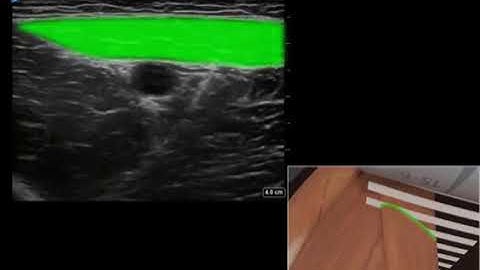

Behind the Scan Webinar - Regional Block Perfection: From Fundamentals to Advanced Skills